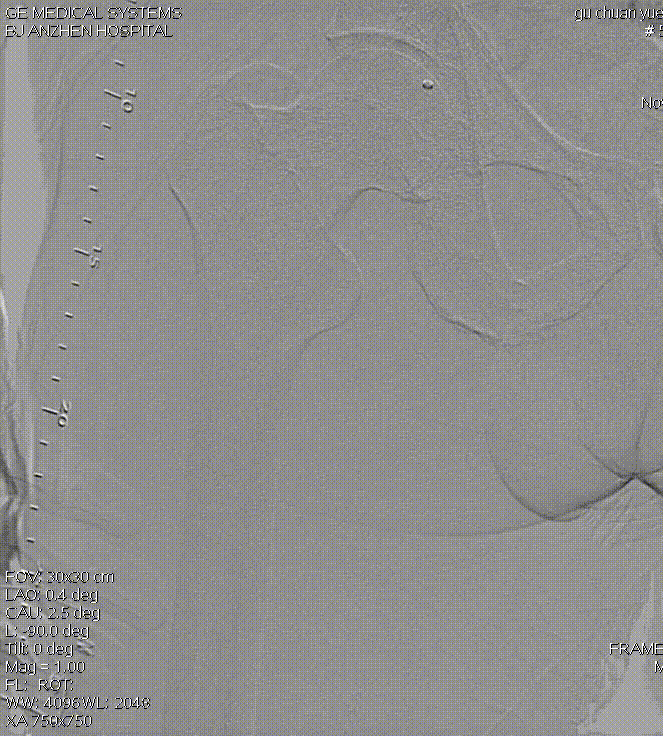

病变类型:严重钙化、长病变

导丝选择:

V-18

Victory™-18,

Asahi Treasure™ 12,

Asahi Astato™ 20,

Asahi Astato™ 30

预扩球囊:

Bantam™ 2x120mm balloon

长期严重钙化

长段严重钙化病变因钙化范围广、质地坚硬,常规扩张治疗易出现血管撕裂、夹层等并发症,且管腔开通效果不佳。定向斑块旋切术凭借 “精准切削、靶向清除” 的核心优势,成为这类复杂病变的优选治疗方案,为临床破解长段钙化难题提供了高效路径。